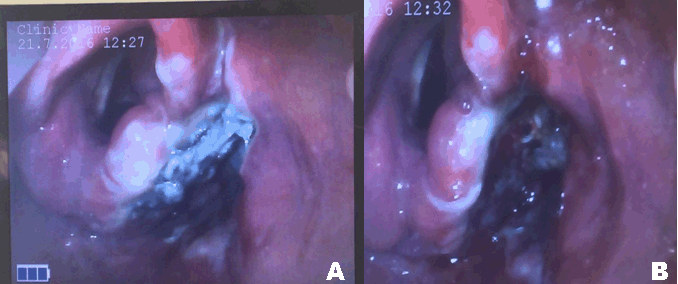

The patient was prepared for examination under general anesthesia and the removal of the foreign body with the assistance of rigid scopes. Examination under general anesthesia in the supine position with full sedation and assistance of a GlideScope, revealed a clear video picture of the metallic foreign body in the right pyriform sinus (Figure 2A). Trial of removal through the GlideScope guidance failed, unfortunately, because of difficulties in directing the instrument towards the metallic foreign body. Then with the use of Macintosh laryngoscope the metallic foreign body was removed by forceps (Figure 3). Re-examination of the site of the foreign body was done again with the GlideScope and suction to the site of the foreign body to ensure there was no perforation (Figure 2B).

Figure 2: (A) GlideScope video laryngoscope image showing steel foreign body located in the right pyriform sinus, and (B) GlideScope image after removal of foreign body.